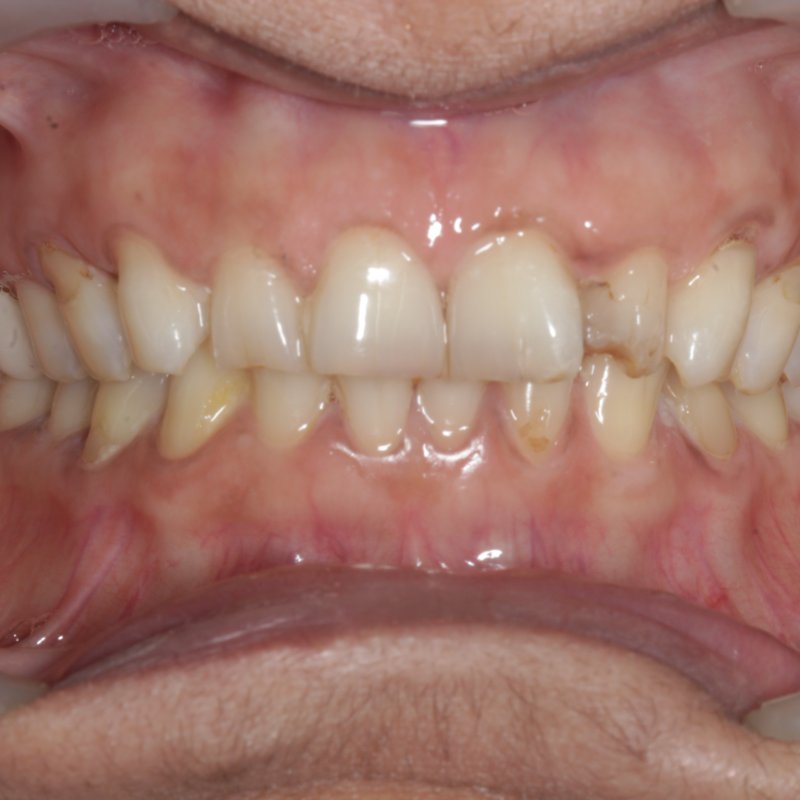

Before full mouth rehabilitation

Smile Makeover

Crown & veneer restoration

Stained, worn dentition restored to a clean, confident smile with porcelain crowns and a refreshed gum line.